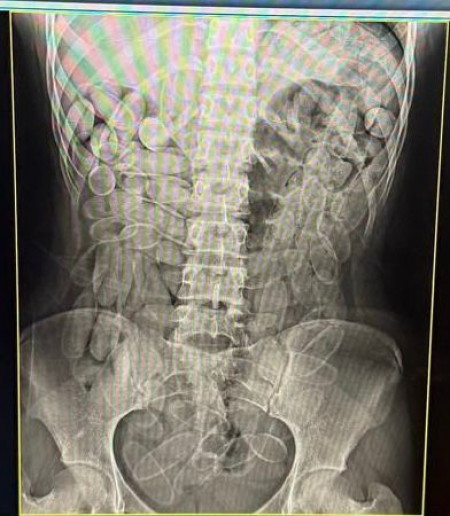

Ambas foram encaminhadas para o pronto-socorro em Corumbá, onde o raio-x apontou a presença das cápsulas e, na sequência, confessaram ter ingerido 102 unidades cada uma.

A apreensão de 204 cápsulas totalizou 2,2 quilos do entorpecente. As duas ficaram sob custódia no hospital e, com a alta médica, foram encaminhadas para as autoridades competentes e responderam pelo flagrante de tráfico de drogas.